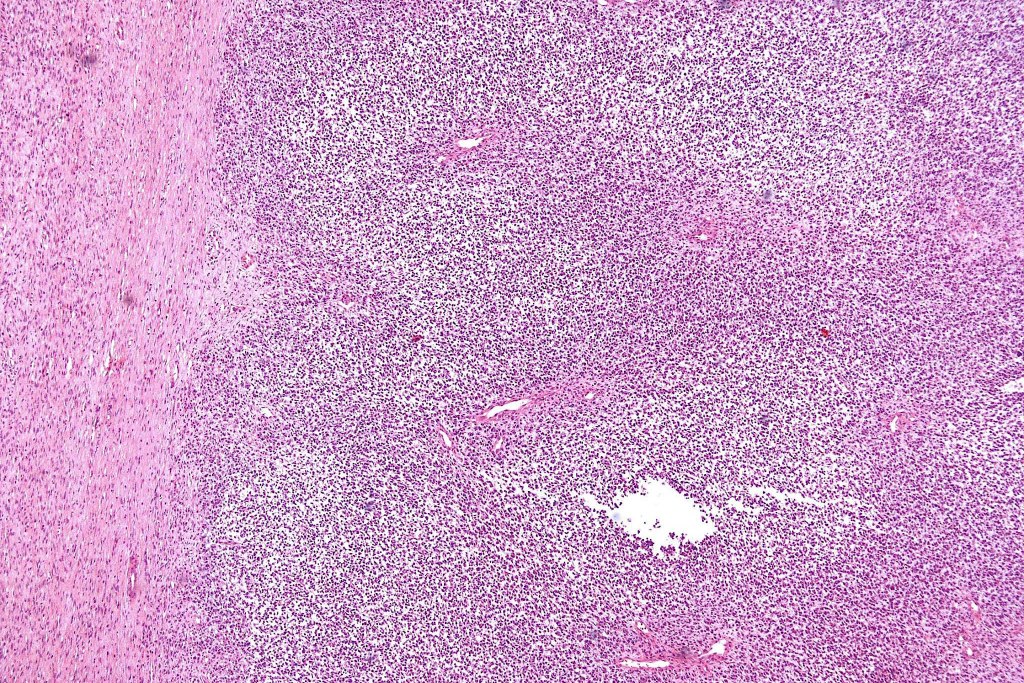

•The nodule generally merges with the adjacent nevus but sometimes it can be sharply circumscribed

•It is hypercellular and most often composed of epithelioid cells showing little pleomorphism & only occasional mitoses

•Nuleoli are small

•The constituent cells are generally larger than the adjacent nevus cells